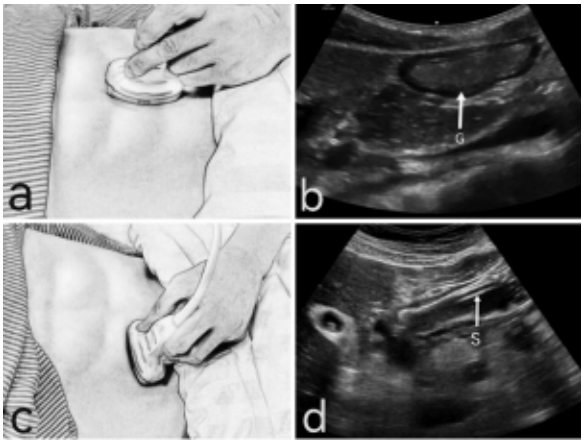

2. 鼻肠管置入幽门及超声定位

(1)继续置入鼻肠管至第一刻度(胃内)处,协助患者取右侧卧位,缓慢置入鼻肠管到达第二刻度处(幽门附近),此时将超声凸阵探头置于患者剑突下,探头标记点朝向头侧(图3a),探查胃窦短轴(图3b),逆时针旋转探头,探头标记点朝向患者右侧,沿患者右侧肋缘下移动,探查胃窦长轴(图3c),判断鼻肠管是否表现为“双轨征”(图3d)。继续向患者右侧移动探头,追溯胃窦至幽门,可依次观察幽门管及十二指肠球部起点,若难以观察,快速注入生理盐水15 ml,幽门处呈现“云雾征”,并向右侧扩散,提示鼻肠管穿过幽门。

图片

图3  鼻肠管置入幽门的超声定位